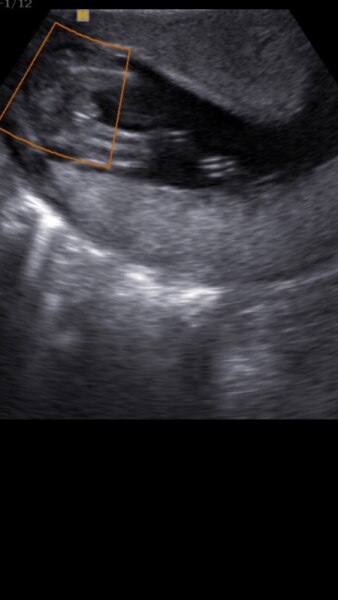

Was meint ihr? Junge oder Mädchen? Mein Bub sah ganz anders aus aber erst 3 Wochen später

...also ohne Fortbildung in Ultraschall-Diagnostik kann ich persönlich da rein gar nichts erkennen. Entscheidend ist doch, was Dein Arzt sagte. Der sollte das Geschlecht in der 17. Woche schon recht zuverlässig erkennen. Bei mir war das Outing beim ersten Kind in der 16., beim zweiten in der 14. Woche. Und beide Male stimmte es auch. LG

Ich finde das sieht nach Junge aus. Hat denn der Arzt nichts gesagt?

Ich würde von Labien ausgehen... die weißen Streifen sind sehr verdächtig...

Wie schon gesagt bei meinem Bub könnte man deutlich den Schnippel vorne sehen daher hätte ich jetzt auch eher Mädchen gesagt

Ich würde auf Junge tippen. Sieht aus wie der Hodensack von unten ...

Ich würde auch eher einen Hodensack sehen, aber keine Ahnung, so wirklich was erkenne ich da nicht und das sind für mich eher wie diese Bilder beim Psychologen, wo jeder was anderes sieht ;) LG Lilly

Ich würd auch sagen Bub. Sag bei unserem Zwerg in der 18.ssw auch so aus. Mittlerweile sieht man es eindeutig ;)

Junge. Von unten zwischen die Beine geschallt . Sichtbar ist der Hodensack.

bei meinen beiden Jungs sah das auch so aus...